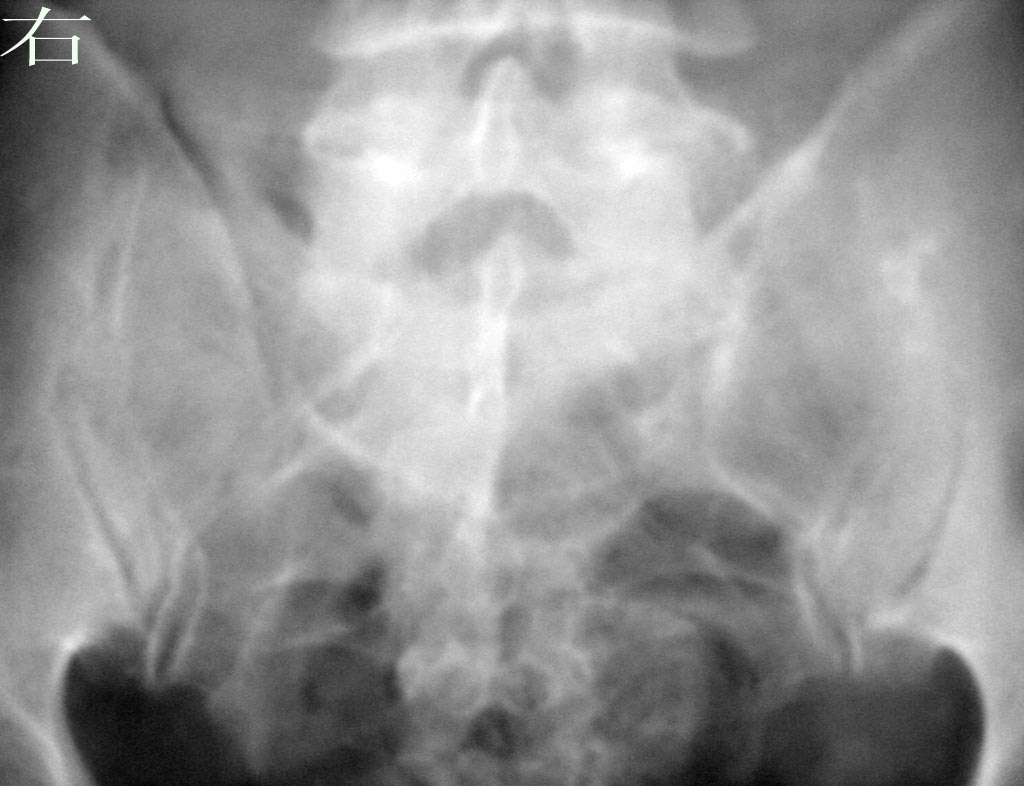

以下是引用拾荒者在2009-10-13 20:19:00的发言:[br]骶髂关节未见明显异常,左侧改变考虑重叠影。

以下是引用zhangzhongshou在2009-10-13 19:43:00的发言:[br]多考虑体位因素所致,必要时ct检查。